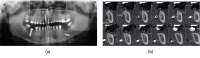

Dental implant surgery is a common procedure in oral and maxillofacial surgery practices. Extensive training, skill, and experience allow this procedure to be performed with an atraumatic approach, but like any surgical technique, it is subject to accidents and complications. This is an unusual clinical case of an accidental displacement of an implant into the submandibular space that progressed to Ludwig's angina, and it has not yet been described in the literature. This case report describes a clinical case of dental implant displaced into the submandibular space after healing cap removal. After seven days, it progressed to Ludwig's angina. The removal was performed through extraoral access in the submandibular area by using hemostatic forceps and radioscopic technique. After implant removal, the clinical case showed a satisfactory repair emphasizing the importance of a meticulous clinical planning to achieve an appropriate treatment plan, which is essential for a favorable prognosis. Therefore, prevention and management of displaced objects requires proper planning and surgical technique.